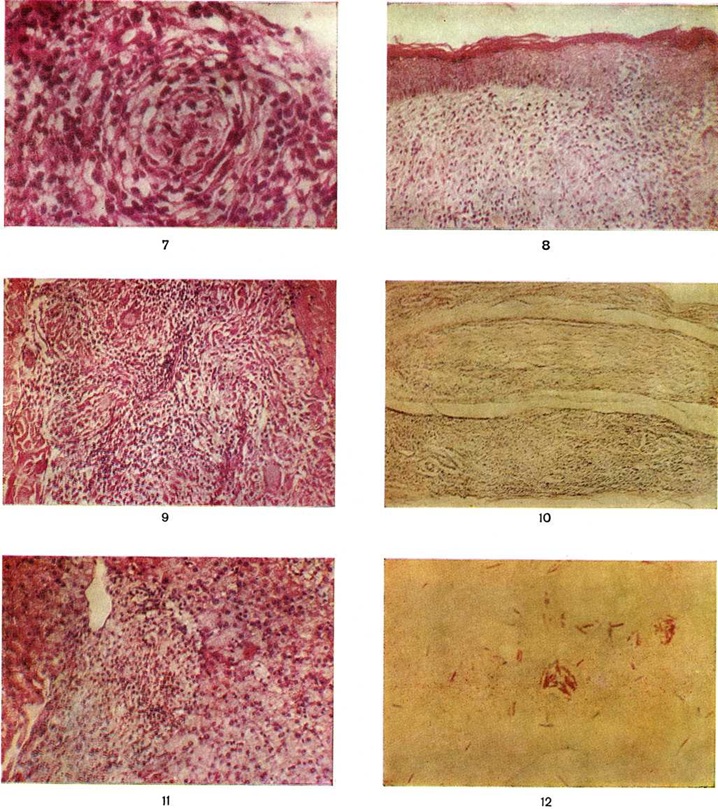

Гистологически лепроматозный тип характеризуется лепроматозной гранулемой кожи, которая представляет инфильтрат, расположенный в сетчатом слое, отделённый от эпидермиса непоражённой зоной коллагеновой ткани. Основными клеточными элементами лепроматозной гранулемы являются лепрозные клетки; кроме того, наблюдаются отдельные плазматические, лимфоидные клетки, единичные фибробласты, многоядерные пенистые клетки (цветной рисунок 1—6). Лепрозные клетки относятся к макрофагам, характеризуются бледным ядром и «пенистой» цитоплазмой (рисунок 5) за счёт содержания липидов. Лепрозный макрофаг на ранних стадиях содержит жирные кислоты, фосфолипиды, ненасыщенные липиды; на стадии развития процесса преобладают нейтральные жиры и кислотные липиды. Большинство исследователей считает, что основная масса липидов представляет собой продукт метаболизма и распада микобактерий Лепра. Наиболее характерная особенность лепрозного макрофага — нахождение и размножение в нем большого количества микобактерий Лепра, то есть явление незавершённого фагоцитоза (смотри полный свод знаний). В цитоплазме лепрозной клетки выявляется высокий уровень окислительно-восстановительных ферментов, кислой фосфатазы, неспецифической эстеразы и не обнаруживается активность липазы. Для гистологический картины LL характерно также наличие капилляров со значительным сужением их просвета за счёт пролиферации и набухания эндотелиальных клеток, содержащих большое количество микобактерий типа «глоби». Кожные нервы пронизаны инфильтратами из микробосодержащих клеток (цветной рисунок 7 и 10). Микобактерии обнаруживаются также в клетках эндоневрия. В лепроматозных поражениях большой давности отмечается частичное или полное разрушение придатков кожи (фолликулов волос, сальных и потовых желёз).

При туберкулоидном типе патологический процесса сформировавшийся инфильтрат может быть массивным, занимающим все слои собственно кожи, или располагаться отдельными очагами. Характерно разрушение субэпидермального слоя коллагеновой ткани с расположением гранулемы непосредственно под эпидермисом с эрозированием последнего. Основную массу гранулемы составляют эпителиоидные клетки (смотри полный свод знаний), расположенные в центре и окружённые по периферии валом из лимфоидных клеток (смотри полный свод знаний Лимфоциты), встречаются гигантские многоядерные клетки типа Лангханса (смотри полный свод знаний Гигантские клетки), в небольшом количестве обнаруживаются плазматические клетки (смотри полный свод знаний), тучные клетки (смотри полный свод знаний), фибробласты. В период обострения в гранулеме наблюдается обилие полиморфно-ядерных лейкоцитов (смотри полный свод знаний). Клеточные элементы не содержат микобактерий и липидов. Характерно утолщение нервных стволов за счёт массивной инфильтрации эпителиоидными клетками.

Морфологически структуры, содержащие элементы, характерные для обоих типов Лепра и являющиеся как бы переходной стадией между полярными типами, характерны для пограничной Лепра При недифференцированной Лепра наблюдается картина банального хронический воспаления (смотри полный свод знаний) без специфических изменений. Основными гистологический критериями, определяющими принадлежность к классификационным группам Ридли — Джоплинга, являются следующие морфологический особенности инфильтрата. 1. Клеточный состав гранулемы. В верхней половине спектра (ТТ, ВТ и ВВ) характерно наличие эпителиоидных клеток (цветной рисунок 8) и для ТТ — многоядерных (гигантских) клеток типа Лангханса (цветной рисунок 9). При ВВ эпителиоидные клетки часто отделены друг от друга отёком. В нижней части спектра (BL и LL) эпителиоидные клетки уступают место макрофагам, цитоплазма которых по мере приближения к типу LL становится более плотной, пенистой и содержит жир. 2. Плотность популяций микобактерий. Количество микобактерий возрастает пропорционально от верхней части спектра к нижней. В числовом выражении показатель бактериальной насыщенности лепроматозного инфильтрата для ТТ, ВТ, ВВ, BL и LL составляет 0/1; 0/2,5; 3/4,5; 4/5,5; 5/6,5 соответственно. 3. Количество и топография лимфоцитов в гранулеме. Для ТТ и ВТ свойственно высокое содержание лимфоцитов, расположенных в виде плотного бордюра вокруг массы эпителиоидных клеток. При ВВ и LL количество лимфоцитов чаще снижено, они рассеяны по гранулеме и не образуют вала. 4. Поражение кожных нервов. Для туберкулоидной части спектра характерно значительное утолщение нерва за счёт массивного инфильтрата (повышение максимального диаметра пучка при ТТ). Для ВВ и BL патогномоничны изменения периневрия в виде луковичной кожуры (onion skin) за счёт расслоения его инфильтратом из лимфоцитов, плазмоцитов (при В В) или бактериосодержащих макрофагов (при BL). 5. Отношение к эпидермису. При ТТ и ВТ гранулема располагается непосредственно под эпидермисом и может эрозировать его. При ВВ, BL и LL между инфильтратом и эпидермисом постоянно остаётся непоражённая зона толщиной 30 — 75 микрометров — так называемый слой Ипа, состоящий из коллагеновой ткани.

Поражение внутренних органов наиболее выражено при лепроматозном типе Лепра Специфические изменения в виде гранулем из макрофагов с высоким содержанием микобактерий обнаруживаются в печени (цветной рисунок 11), селезёнке, костном мозге, слизистой оболочке верхних дыхательных путей, яичках, надпочечниках, лимфатических, узлах. В материале, полученном при пункции периферических лимфатических, узлов, обнаруживаются микобактерии Лепра; в паракортикальной области выявляются скопления недифференцированных макрофагов, содержащих большое количество микобактерий; зародышевые центры хорошо развиты, а мозговые тяжи заполнены плазматическими клетками.